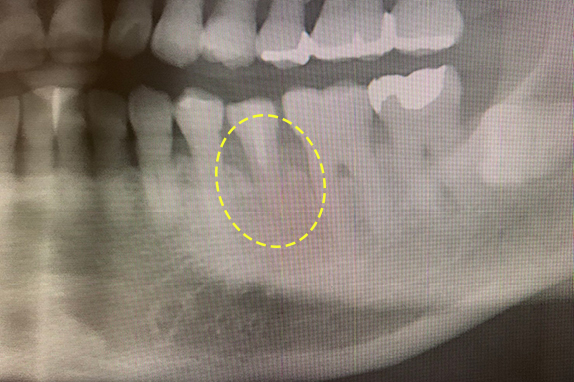

CASE 01 歯周再生治療

-

- 主訴

- 歯がグラグラで噛めない

-

- 回数期間

- 5回 約1年

-

- 治療法

- 歯周再生治療

-

- 治療費用

- 約17万円(税抜)

歯がグラグラで噛めないという主訴の患者様に歯周再生治療を用いて改善したケースです。レントゲン写真をみると術前は歯肉の退縮が見られるが、術後は歯肉の退縮が改善しています。

<リスク・副作用>

手術後は腫れ、痛み、痺れなどの副作用が生じる場合があります。